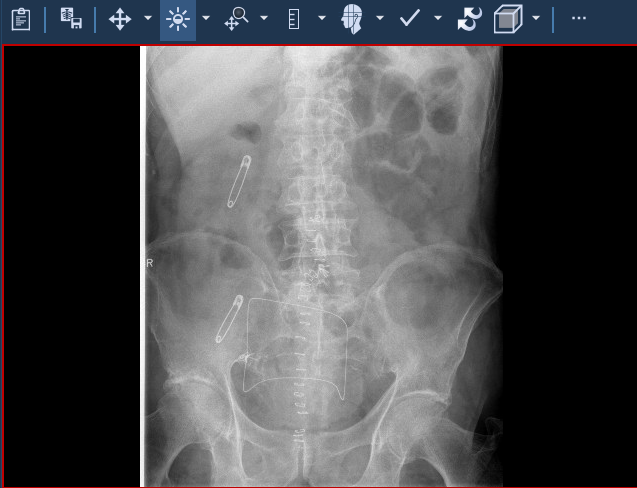

Εξέταση ασθενούς όπου αποκρύπτονται οι δημογραφικές πληροφορίες ![]() | Εξέταση ασθενούς όπου εμφανίζονται οι δημογραφικές πληροφορίες (σε κύκλο) ![]() |